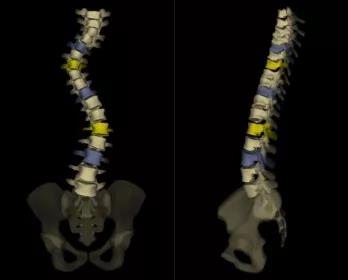

法國EOS X射線影像采集系統(tǒng)

?諾貝爾物理學獎的新型X射線探測技術;

?實現(xiàn)了人體1:1真實成像;

?是非拼接全脊柱、全下肢一次性成像X線設備;

?僅需0.05mSv(約一張胸片的劑量)即可完成全脊柱正側位成像。

?正側位全長影像一次掃描成像的優(yōu)點:負重位正交同步拍攝、線性掃描1:1全長片、動態(tài)自動增益控制;

?雙球管正側位同步拍攝:一次掃描同時獲得正、側位影像,消除兩次拍攝的系統(tǒng)誤差;

?精準的線性掃描:幫助醫(yī)生對脊柱、關節(jié)等相關骨骼疾病進行術前診斷、制定手術計劃、評估手術效果、跟蹤隨訪以及相關科研工作;

?不失真高質量圖像:全身視圖1:1。

脊柱側彎